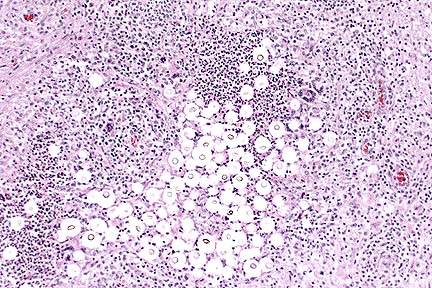

Granulomatous encephalitis with the classic "soap-bubble" appearance associated with Cryptococcus neoformans in the cerebrum of a horse. (HE, 100X, 65K)

The brain contained numerous encapsulated yeast bodies compatible with C. neoformans. Similar organisms were present in the lung within the grossly visible nodules. Lesions in the lungs were those of pyogranulomatous pneumonia. This case is somewhat unusual, because in the CNS 1) C. neoformans is usually associated with meningitis and 2) the organism usually evokes minimal inflammatory response. In this case, lesions were confined to the midbrain; the meninges were spared.

Conference Note: Cryptococcus neoformans is a yeast-like fungus in tissue. It reproduces by single buds, is 4-8 æm in diameter, and is surrounded by a thick mucopolysaccharide capsule. The capsule stains well with mucicarmine and alcian blue and is PAS-positive. Cryptococcosis occurs worldwide; the source of the infection is believed to be soil, especially in areas contaminated by pigeon or other bird feces. All species of animals can be affected, but cats are affected more often than other domestic animals.

Histologically, the lesion is described as having a "soap-bubble" appearance, the result of the thick, nonstaining, capsule. The inflammatory response to cryptococcosis is usually minimal, consisting of macrophages, lymphocytes, and plasma cells. Occasionally, a granulomatous reaction will develop, especially in the lungs.